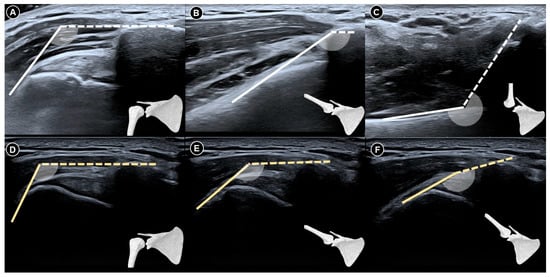

Figure 6. Dynamic ultrasound images of a normal shoulder captured at neutral resting position (A), during abduction beyond 90 degrees (B), and at full elevation to 180 degrees (C). Corresponding images of a shoulder with adhesive capsulitis at rest (D), abduction past 90 degrees (E), and maximal abduction (F). The figure was redrawn by the authors with reference to Chang et al. [35].

Recently, Chang et al. [35] introduced the humerus-acromion angle model to assess adhesive capsulitis severity by quantifying scapulohumeral rhythm during shoulder abduction. Normally, it follows a 2:1 ratio—every 3° of elevation involves 2° at the glenohumeral joint and 1° from scapular rotation. During ultrasound, positioning the probe along the acromion, while the patient abducts the arm, reveals a progressive angle increase between the acromial cortex and the humerus, ranging from ~120° at rest to ~240° at full abduction. This change reflects both glenohumeral rotation and inferior humeral translation. In frozen shoulder, this angle plateaus prematurely despite passive elevation, indicating impaired glenohumeral motion. Further abduction then depends on limited scapular rotation (~60°). This model offers a more precise means to evaluate mechanical constraints in glenohumeral adhesive capsulitis (Figure 6).